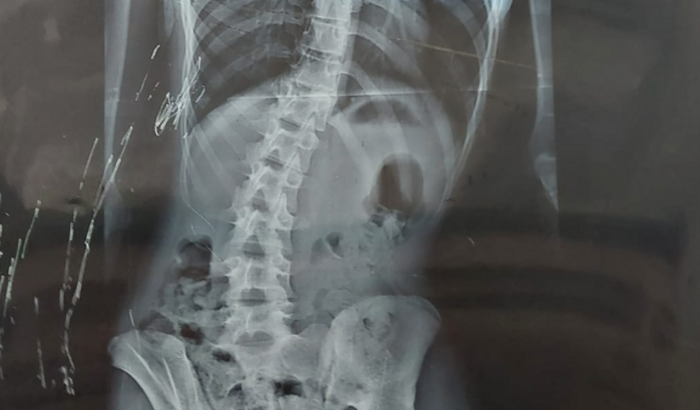

Eu sou a Priscila, preciso comprar um colete para escoliose S4D, para a minha filha Geovana, pagar a fisioterapia e natação.

Ela tem 14 anos, está afastada da escola, pois, sem o colete e as fisioterapias e a natação, ela não consegue se locomover, sente dor ao caminhar.